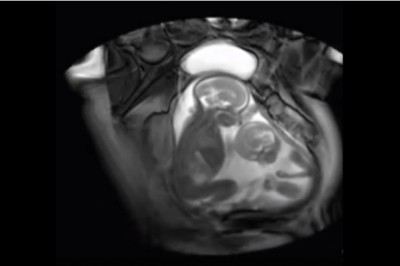

Niesamowite zdjęcia bliźniaków w łonie matki walczących o miejsce! Cudowne!

Zastanawialiście się kiedyś jak dziecko układa się w łonie swojej matki? A co w wypadku, gdy tę niewielką przestrzeć muszą dzielić bliźniaki? Może się zrobić dosyć ciasno.Te fascynujące nagranie bliźniaków walczących o swoje miejsce, szybko stało się popu...